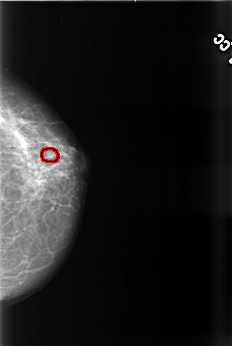

B_3471_1.LEFT_CC

LEFT_CC LINES 4488 PIXELS_PER_LINE 3008 BITS_PER_PIXEL 12 RESOLUTION 50 OVERLAY

FILE: B_3471_1.LEFT_CC.OVERLAY

TOTAL_ABNORMALITIES 1

ABNORMALITY 1

LESION_TYPE CALCIFICATION TYPE PUNCTATE DISTRIBUTION CLUSTERED

LESION_TYPE MASS SHAPE ROUND MARGINS MICROLOBULATED

ASSESSMENT 4

SUBTLETY 3

PATHOLOGY BENIGN

TOTAL_OUTLINES 1

BOUNDARY